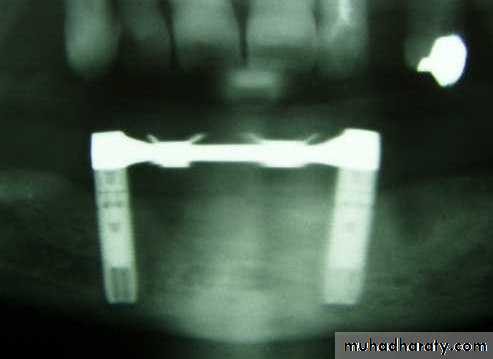

Two-Implant Bar Overdenture